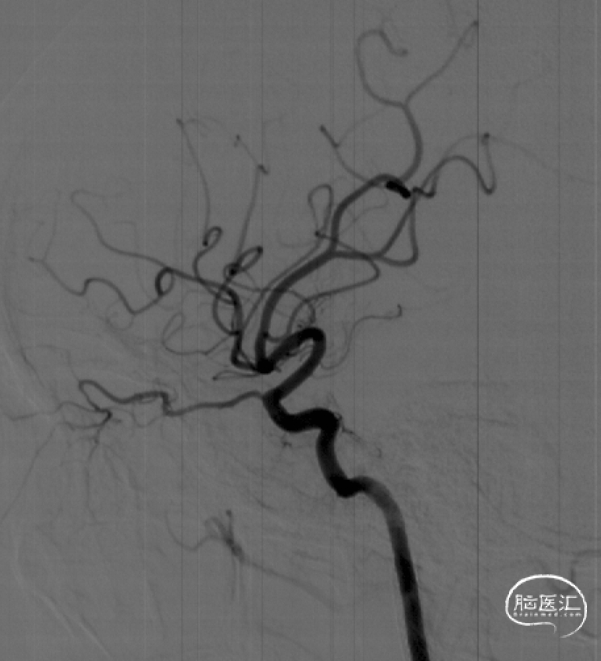

2024-06-06 DSA:左侧A1纤细,通过前交通向右侧少量代偿供血

椎动脉造影提示后循环通过软脑膜支及胼周动脉代偿右侧前循环

右侧颈总动脉造影见颈外动脉通过眼动脉向颅内代偿,颈内动脉闭塞,Hasan分型B型

6F Envoy导引导管到位后,微导丝通过闭塞段,引导微导管到达C6段,造影确认真腔

璞慧微导丝技术送至M1段,撤出微导管送入Sacspeed 2.5/15:Sacspeed 2.5mm/15mm球囊自远及近扩张

球扩成型后,依次植入Wallstent 7/50、7/30

C1段支架成型满意,但C3段仍狭窄,植入Apollo 3/23球扩支架